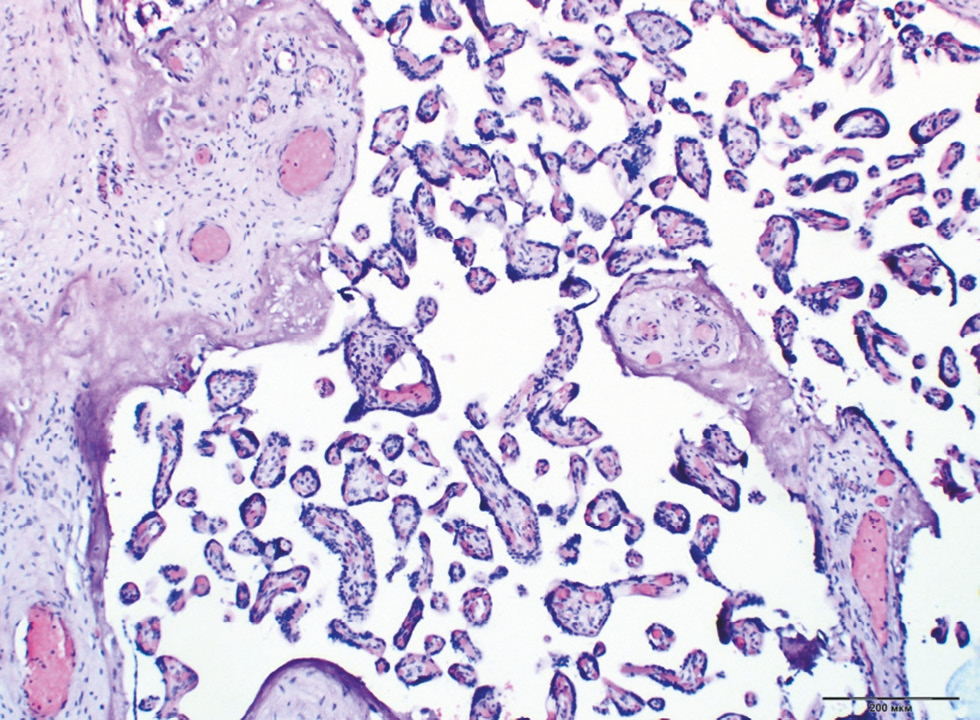

When assessing placental insufficiency, acute circulatory disorders were detected more often in patients from the GDM group on a diet (Group 5), that is, in 11.6% of cases. In addition, compensated (23.1%) and subcompensated (17.9%) placental insufficiencies were most typical for PE (p < 0.0001) (Fig. 6). Decompensated placental insufficiency was registered in two cases in Group 5, and the differences did not achieve statistical significance (p = 0.96).

Fig. 6. Hypoplastic form of chronic placental insufficiency. Staining with hematoxylin and eosin, ×100